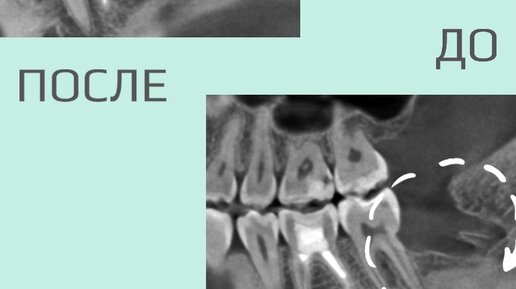

Как долго заживает рана после удаления зуба?

Срок регенерации зависит от сложности операции, возраста и состояния здоровья пациента. Если следовать всем рекомендациям хирурга, то частичное заживление слизистой происходит примерно за 12 дней. Полное восстановление десны наступает через 20–25 дней...